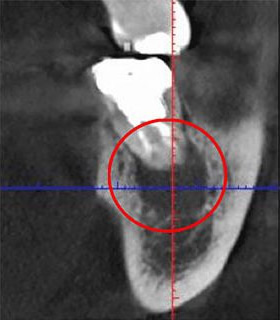

根管は狭く複雑で、目に見えない部分に存在します。当院では、根管の形状を正確に把握するために「CT」を利用しています。CTは360度回転しながら撮影を行うため、立体的かつ鮮明な画像を提供します。以下に、CTと従来のレントゲン撮影の画像比較を示します。

同じ患部をCTで撮影したもの(左)と、レントゲンで撮影したもの(右)です。CTで撮影した黒い影は、炎症を示していますが、レントゲンで撮影したものには炎症は見られません。

CTでしか確認できない初期の炎症も見逃さずに、より精密な診断を行うことができます。